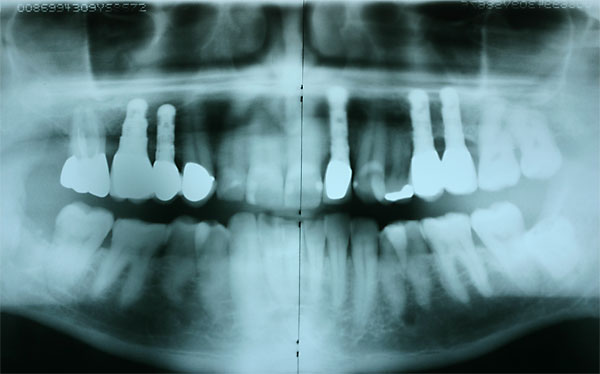

FOTO Abschlußröntgenbild der Versorgung |

Fall: festsitzender Zahnersatz im Oberkiefer auf 8 Implantaten